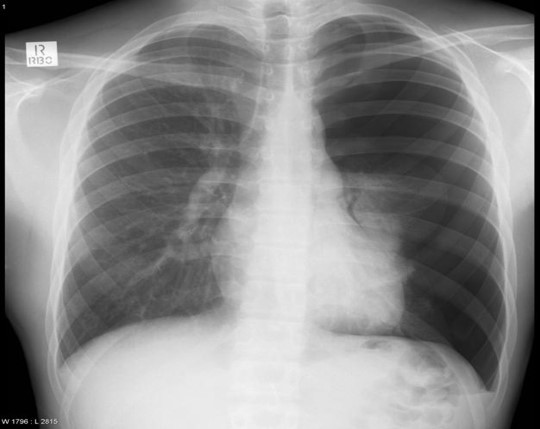

Right Tension Pneumothorax w/

Left Tension Pneumothorax

Flattening of left diaphragm

Deviated to the right

Left pneumothorax